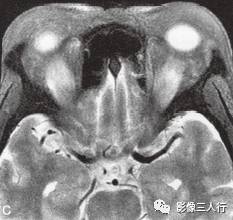

A~C.抑脂T2WI横断面;D~F.T1WI横断面;G~H.T1WI冠状面;I.抑脂T2WI冠状面

横断面显示双侧眼球明显突出,双侧眼球角膜至双侧颧突连线的垂直距离分别为:右侧2.2cm、左侧2.3cm。双侧眼外肌明显增粗,以双侧内、外、上、下直肌明显,短径均可达7mm,且以肌腹增粗明显呈梭形,T1WI等信号(图D~F,图G~H),抑脂T2WI呈明显高信号(图A~C,图I)。双侧眼眶内及球后脂肪增多,双侧眼球内侧至眼眶内侧壁的脂肪厚度增宽。双侧视神经形态及走行正常,双侧眼球晶体、玻璃体形态及信号正常。

影像学检查可帮助该病的诊断与鉴别诊断。CT表现为眼外肌增粗,主要为肌腹增粗,附着于眼球壁上的肌腱不增粗,少数也可同时累及眼外肌肌腹和肌腱。最常累及下直肌,其次为内直肌、上直肌和上提肌,偶尔累及外直肌。MRI表现为受累的眼外肌T1WI低信号,T2WI高信号,压脂T2WI为高信号;晚期眼外肌已纤维化,在T1WI和T2WI均呈低信号。增强扫描急性期时增粗的眼外肌有轻至中度强化,晚期眼外肌纤维化时则无强化。眶内脂肪体积增多表现为球周脂肪尤其是眶前部脂肪的增多。本例影像征象较典型。